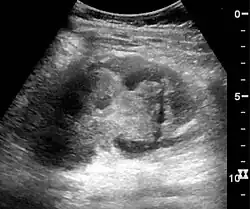

In medical imaging, the acute changes in the kidney are often examined with renal ultrasonography as the first-line modality, where CT scan and magnetic resonance imaging (MRI) are used for the follow-up examinations and when US fails to demonstrate abnormalities. In evaluation of the acute changes in the kidney, the echogenicity of the renal structures, the delineation of the kidney, the renal vascularity, kidney size and focal abnormalities are observed.[20] CT is preferred in renal traumas, but US is used for follow-up, especially in the patients suspected for the formation of urinomas. A CT scan of the abdomen will also demonstrate bladder distension or hydronephrosis.[21]

Renal ultrasonograph of acute pyelonephritis with increased cortical echogenicity and blurred delineation of the upper pole[20] -

Renal ultrasonograph in renal failure after surgery with increased cortical echogenicity and kidney size. Biopsy showed acute tubular necrosis.[20] -

Renal ultrasonograph in renal trauma with laceration of the lower pole and subcapsular fluid collection below the kidney[20]